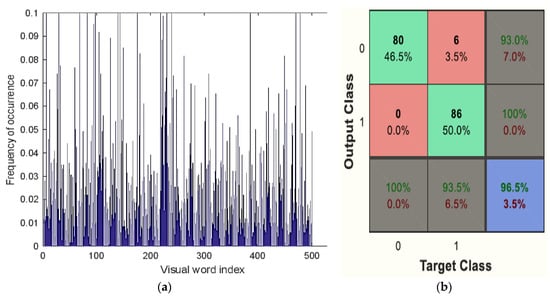

Ultimately, the Bag of Visual Word classifier’s classification results showed whether the picture was benign or malignant. Figure 11a,b shows the Bag of Visual Word results plot. This classifier shows the outcome of detection of benign classification in Figure 9 and malignancy classification in Figure 10.

Figure 11.

(a) Visual vocabulary of BoVW classifier, (b) Confusion matrix of BoVW classifier.

The obtained accuracy after optimisation was 98.5%. Table 6 analyses performance parameters for the BoVW and CRNN classifiers. The parameters considered here are accuracy, sensitivity, specificity, precision, PSNR and MSE values. For the BoVW classifier, accuracy was 96.5%, sensitivity was 93%, specificity was 100%, precision was 93.5%, PSNR value was 42.278, and the MSE was 3.474. For the CRNN classifier, accuracy was 98.5%, sensitivity was 95%, specificity was 100%, precision was 95.5%, PSNR was 69.154, and the MSE was 2.193. From Table 6, it is clear that CRNN provided the best output performance in terms of accuracy and precision. Table 7 shows the error and accuracy comparison regarding different classifiers. Figure 15 shows (a) the Performance Measure of the classifier and (b) the Performance Graph of the classifier.